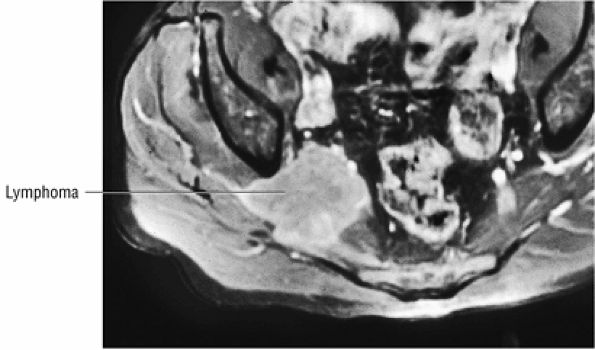

The sciatic nerve, located directly posterior to the posterior column of the acetabulum, demonstrates intermediate signal intensity. It exits the pelvis through the greater sciatic foramen (the greater sciatic foramen is bordered by the ilium, the rim of the greater sciatic notch, the sacrotuberous ligament, and the sacrospinous ligament) inferior to the piriformis muscle.

The external iliac vessels, which are of low signal intensity, are medial to the iliopsoas muscle and anterior to the anterior acetabular column.